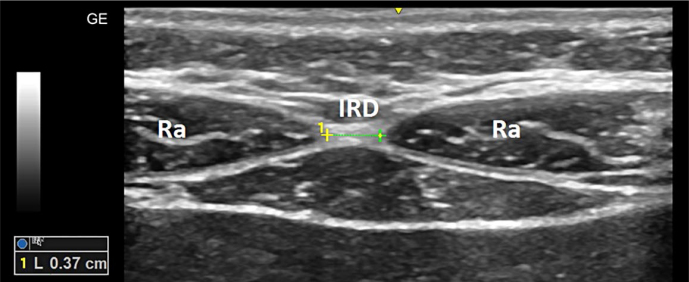

Material and methods: Anatomy of the rectus abdominis muscles and the linea alba, with a special focus on the interrectus distance (distance between two bellies of the rectus abdominis muscles), was studied using ultrasound. Anthropometric and ultrasonographic assessments were performed on 38 children aged 7-12 years. According to the clinical definition of bulging in the epigastrium, diastasis was diagnosed in 12 children (31.6%), significantly more often in boys than in girls (50.0% vs. 6.3%). Other clinical and anthropometric variables, such as age, history of preterm birth, body mass, body mass index, waist circumference, and height, were not significantly associated with diastasis recti.

Results: Diastasis recti, defined by the ultrasonographic criterion of interrectus distance >20 mm, was found in 10 children (26.3%), with no significant differences between boys and girls. Still, there was a moderate agreement between these two modes of diagnosing diastasis: the Cohen's kappa coefficient was 0.49. This suggests that ultrasonographic measurement of the interrectus distance should not be considered an alternative and more precise method of diagnosing diastasis.